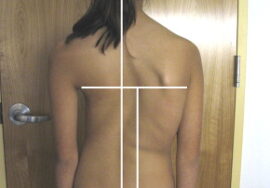

كيف تكتشف اعوجاج العمود الفقري مبكرًا عند طفلك؟

من المهم أن يكون الأهل على وعي بالعلامات المبكرة، ومنها:

تفاوت في مستوى الأكتاف.

بروز أحد جانبي الصدر أكثر من الآخر.

ميل الجسم إلى أحد الجانبين.

عدم تساوي الخصر أو الوركين.

في حال ملاحظة أي من هذه العلامات، يجب استشارة الطبيب على الفور لعمل فحص سريري وتصوير بالأشعة إذا لزم الأمر.